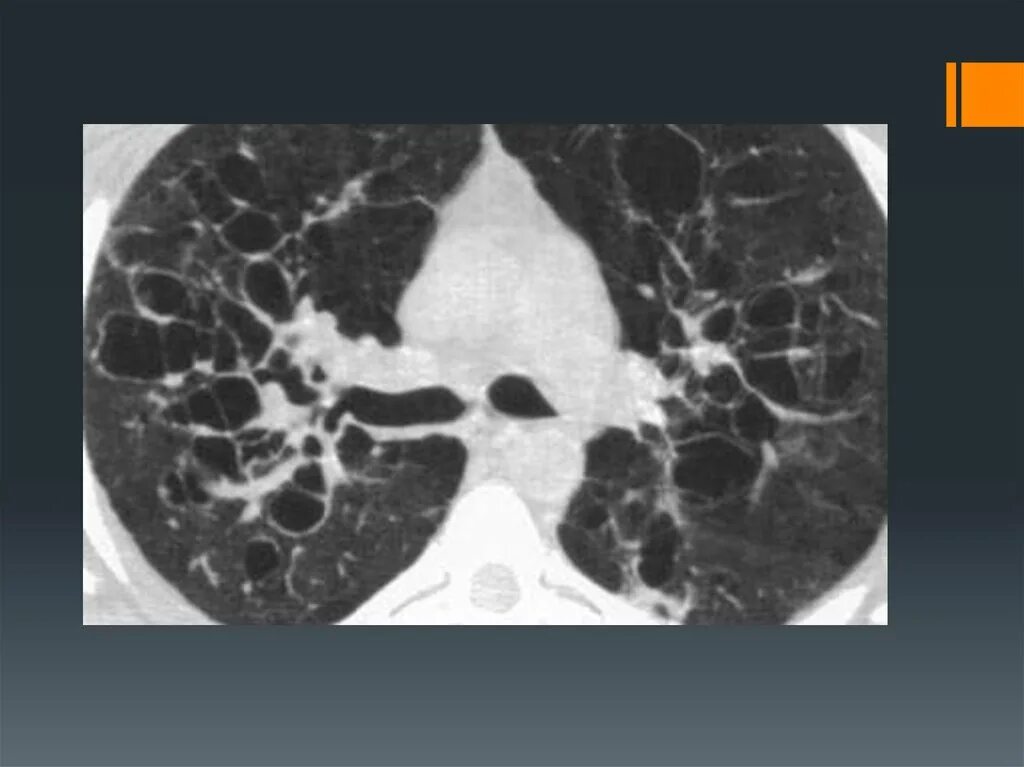

Заболевание кт